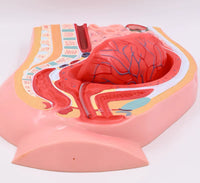

Modelo de desprendimiento separacion de placenta

Este modelo es una sección sagital del abdomen y la cavidad pélvica femenina con volumen uterino y superficie de inserción pélvica reducidos después del parto, que muestra la estructura morfológica del útero, la vagina, la placenta y el cordón umbilical.

Las superficies fetal y materna de la placenta tienen una forma realista, la parte inferior del útero está ligeramente hacia arriba y continúa contrayéndose, cerca del bulto abdominal inferior de la sínfisis del pubis y el cordón umbilical que cuelga en los genitales (signos de desprendimiento de placenta). ).

se desprende la parte central de la placenta y se baja al segmento inferior de la cavidad uterina.